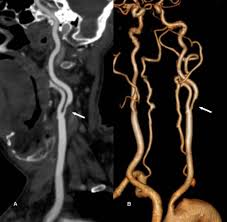

Quảng Ninh: Đặt stent mạch cảnh cứu cụ ông đột quỵ lần 2

Cụ ông 87 tuổi (Quảng Ninh) lên cơn nhồi máu não lần 2 trong 3 tháng, đã được các bác sĩ Bệnh viện Đa khoa tỉnh Quảng Ninh cấp cứu điều trị kịp thời.